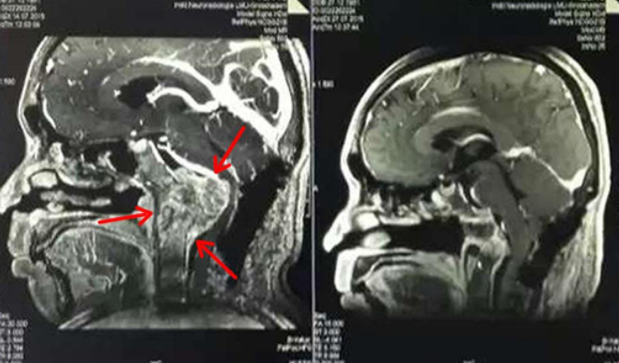

自20世纪70年代末以来,脊索瘤的治疗传统上依赖于整块切除;这项技术对于骶骨脊索瘤是合适的,但是它的适用性在斜坡脊索瘤中很明显是有限的。根治性切除肿瘤及其胶囊剂已被证明比次全切除合适得多,因为它减少了细胞播散的范围,从而降低了复发的风险。但是斜坡脊索瘤由于其不同位置,又是难以切除干净的,所以容易复发。在脊索瘤手术上,INC国际神经外科医生集团成员德国巴特朗菲教授、法国Sebastien Froelich教授、加拿大James T. Rutka教授可以对脊索瘤较大水平切除,延缓复发速度,或少复发;且术后无神经功能损伤。

目前前沿的术中成像技术,包括CT和MRI扫描,可以早期发现小的骨内肿瘤并将其完全切除。由于脊索瘤是一种具有抗辐射能力的肿瘤,因此放射治疗常与手术联合使用,主要依靠大剂量的质子束,在程度上,也可依靠氦离子或碳离子治疗。对于质子治疗,德国慕尼黑里雷克质子治疗中心(RPTC)是出名的,德国作为国际医疗强国,从 1989 年起, 慕尼黑里雷克质子治疗中心(RPTC)便首先开展了质子治疗,成了质子治疗领域全国际规模较大的病例库。